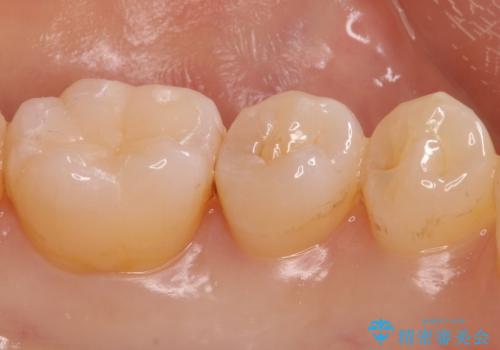

- 奥歯の樹脂の色が気になるとのことで来院されました。

変色しない材料での治療をご希望されたためセラミックインレーでの治療をしていくこととなりました。

継ぎ接ぎになった樹脂の詰め物から一塊のセラミックインレーに置き換えることで着色や二次う蝕のリスクを抑えます。